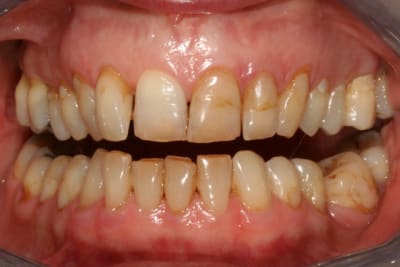

cette patiente que je suis en controle depuis 2 ans, se décide à faire quelque chose pour son sourire.

grosso modo depuis 2 ans, pas de soucis particuliers, pas de caries, faut faire un peu gaffe à la paro mais elle est plutôt motivée et ça se passe bien.

elle a plein de vieux compos d'une mauvaise couleur, au joints colorés, des dents de couleur pas vraiment toutes pareilles ; et un sourire très gingival.

je ne sais pas trop d'ou ça viens, de mylolyses traitées au compo ou d'un épisode de caries au collet ?

elle ne fume pas, bois du thé, un peu de café.